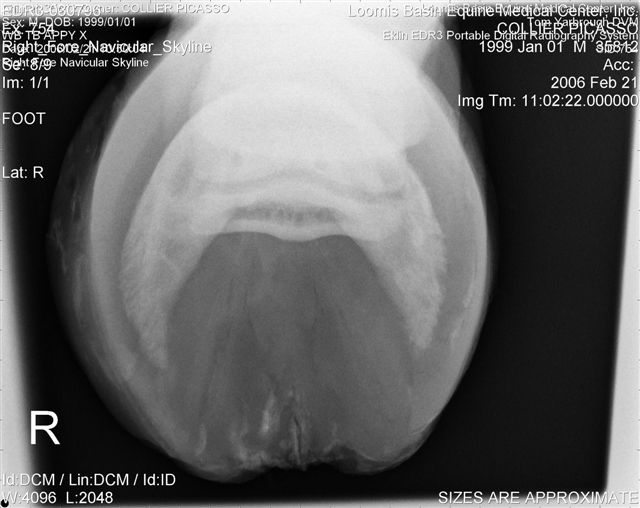

Let's label the radiographs from left to right with numbers. The abnormalities I see on the L using the photo's number as reference:

On the right the main problem is the appearance of the n. bone in the first image. It appears to have large irregular areas of increased lucency surrounding areas of decreased lucency. The darker areas (decreased lucency) may be artifacts or represent thinning of cortical bone.

Unless there is something I am missing in the images the extensor process appears to have healed well on the L. The significance of each of these lesions will depend on clinical findings Ann and confirmation that these are actual lesions and not artifacts created by positioning or the foot preparation for radiography. You should note I am not a radiologist and that viewing images in this manner is not as revealing as viewing the radiographs first hand.

No I don't think squaring will put more stress on the extensor process and the R looks pretty well aligned. Concerning the R navicular bone see my comment above.